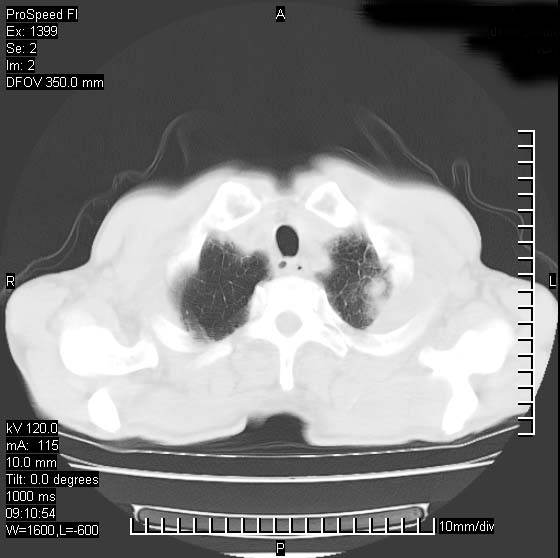

以下是引用卜一在2007-1-19 9:55:00的发言:[br]左肺沿胸膜下巨大肿块影,边缘呈分叶征,纵隔内见肿大淋巴结,右肺内另见一不规则结节影 .考虑:左肺周围性肺癌伴纵隔 右肺内转移.